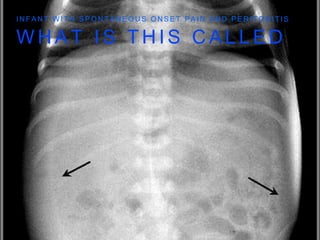

W H A T I S T H I S C A L L E D

I N F A N T W I T H S P O N T A N E O U S O N S E T P A I N A N D P E R I T O N I T I S

F O O T B A L L

S I G N

• ALSO A SIGN OF FREE

AIR IN THE PERITONEAL

CAVITY

C A N Y O U S E E T H E F O O T B A L L

A N D T H E D O U B L E W A L L

S U P I N E V I E W

W H AT I S T H I S C A L L E D I N F A N T W I T H S P O N T A N E O U S O N S E T P A I N A N D P E R I T O N I T I S

F O OT B A L L S I G N • ALSO A SIGN OF FREE AIR IN THE PERITONEAL CAVITY

C A NY O U S E E T H E F O O T B A L L A N D T H E D O U B L E W A L L S U P I N E V I E W